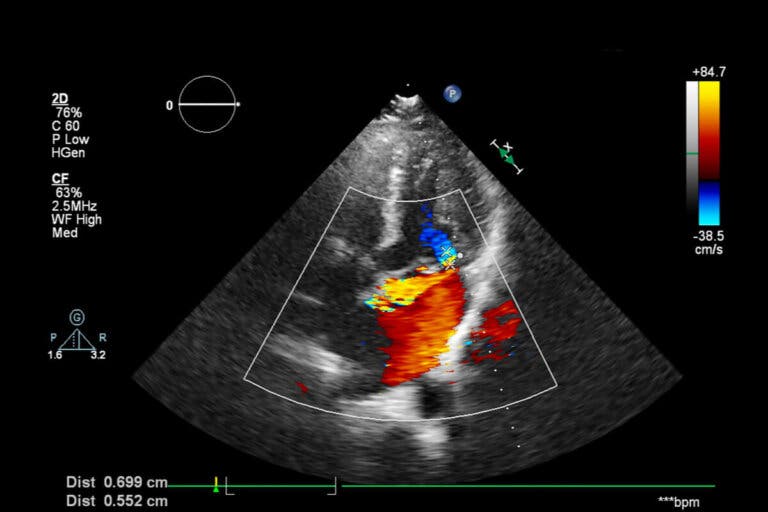

En esta ecografía a color, una computadora otorga tonos a las ondas sonoras y cada uno de ellos expone en tiempo real la dirección y la velocidad de la sangre.

En la forma Doppler de la ecografía se visualiza el flujo sanguíneo en tonos rojos y azules.2. Dúplex